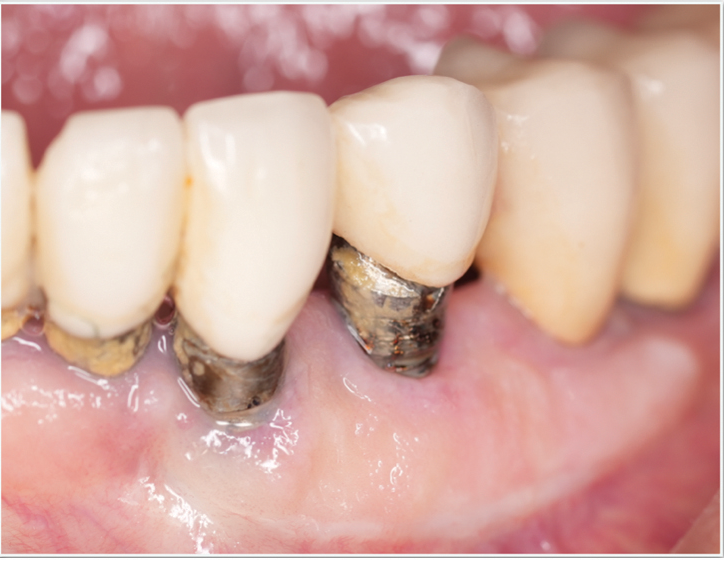

Fig 2. A patient presented with inflammation around implants. The patient was having difficulty brushing the area due to a shallow vestibule, the proximity of the implants, and a lack of keratinized tissue surrounding the implants.

Figure 2

Tissue thickness has been shown to affect the initial crestal bone loss around dental implants.33 Linkevicius et al demonstrated that thick phenotypes had less initial crestal bone loss than thin phenotypes.33 However, when thin tissues were augmented with human soft tissues (allografts), the crestal bone loss was comparable to thick tissues.33 Therefore, a thicker phenotype is more desirable when evaluating soft-tissue quality around dental implants, and this aspect should be evaluated during maintenance visits. Additionally, the amount of keratinized tissue may affect the long-term prognosis of dental implants. In natural dentition, at least 2 mm of keratinized tissue reportedly is necessary to maintain health of the periodontal tissues.34,35 For dental implants, however, the significance of keratinized tissue in preserving implant health has been less clear, with some early studies showing no association between the amount of keratinized tissue and bone loss and some studies reporting that the presence of keratinized tissue significantly decreases the amount of recession and clinical attachment loss.34-36 Additional studies support a band of keratinized tissue of more than 2 mm to be associated with decreased BOP, plaque, mucosal recession, and attachment loss,34,37 especially when patients are not on a strict maintenance protocol.38 This may be because keratinized tissue provides increased comfort for the patient during home care regimens, whereas pain with brushing and therefore a reluctance to upkeep maintenance may occur with thin peri-implant mucosa (Figure 2).39 As a result, during supportive peri-implant therapy, adequate evaluation of soft-tissue quality around dental implants is crucial, with recommendations for soft-tissue augmentation if needed (Figure 3 and Figure 4).